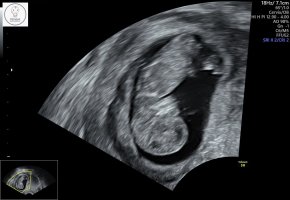

Netopp vært på ultralyd og oppfølging på sykehuset , blir tettere oppfølging nå og jeg kan bare ringe og kome om det er noe.ikke tegn til noe mer blødning nå , sannsynligvis har det blødd ut men alikevel var de ikke helt sikker..men såg bra ut. Lille sprella og hjerte slo. Alt bare fint. Har litt veske i buken og cyster etter ivf stimulering som de også vil følge ekstra opp.. veldig flink og hyggelig lege . Og veldig gla alt sto så bra til. ❤️❤️og at helsevesenet funker så blir ekstra ultralyder dær også.